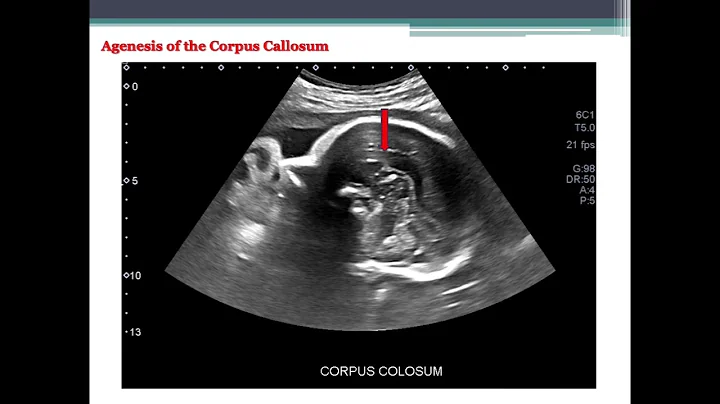

Anomaly Scan (18-22 Weeks) | Dr. Siddhartha Sharma | Consultant Radiologist At Dg Diagnostics

Welcome to the official DG Diagnostics YouTube channel! I'm Dr. Siddhartha Sharma, a Consultant Radiologist, and in this video, ...